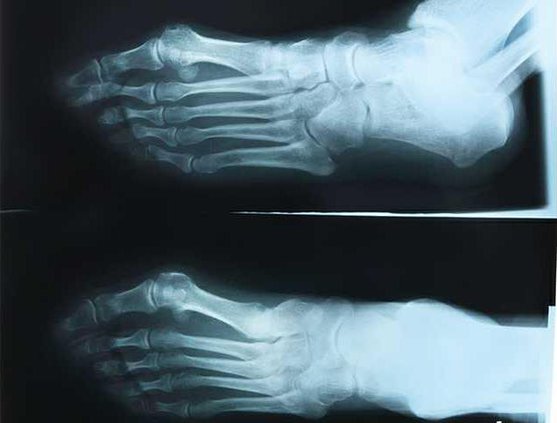

bone xray

Researchers at the Medical College of Georgia at Georgia Regents University are looking for ways to reduce bone loss from arthritis and its treatment. - photo by Stock photo